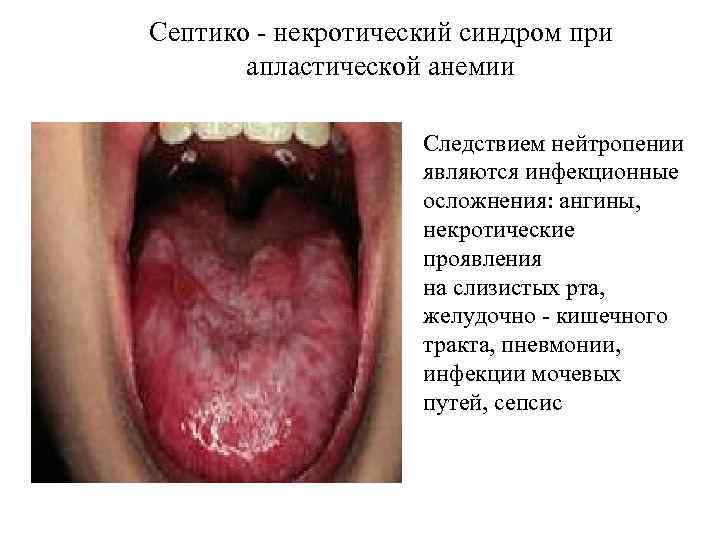

Септико - некротический синдром при апластической анемии Следствием нейтропении являются инфекционные осложнения: ангины, некротические проявления на слизистых рта, желудочно - кишечного тракта, пневмонии, инфекции мочевых путей, сепсис